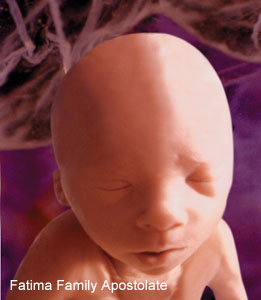

25 haftalık bebek Bebeğinizin boyu 30 cm oldu. İç kulağındaki kemiklerde sertleşmeye başladığından artık sizi daha iyi duyabiliyor. Aslında babasının sesini, sizin sesinizden daha net duyabiliyor. Eşinize söyleyin, karnınıza yaklaşıp bebeğinize “Merhaba” desin lütfen !